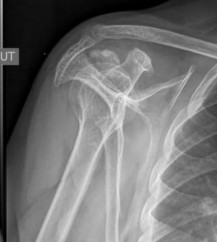

X-Quang khớp vai nghiêng kiểu Lamy cho phép thấy hố trên gai và dưới gai, cho thấy gián tiếp toàn bộ CX bao quanh chỏm xương cánh tay, cho phép định vị được khối calci hoá cơ CX, thấy lỗ rách gân CX khi có bơm thuốc cản quang, phân tích được hình dạng của phần xa của mỏm cùng, mỏm quạ và xương bả vai.

Hình 1.21. Minh họa calci hóa gân CX khớp vai nhìn trên tư thế Lamy

Nguồn: Theo nguồn AAOS (American Academy of Orthopaedic Surgeons)